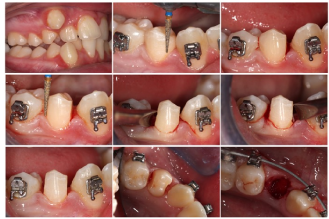

Only after the tooth has shown some root dislocation and mobility, the tooth can be loosened in backward posterior direction, limiting in this way the amount of reaction force applied to the front teeth. (Figure 4)

Figure 4. Extraction technique: socket preservation avoiding periodontal trauma

Special care at this point, is required to not dislocate roots towards the labial bone. Clockwise alternated to counter clockwise movements gradually lead to root removal. (Figure 5)

Figure 5. Additional procedures when removing teeth with multiple roots; close detail of the thin preserved labial cortical plate